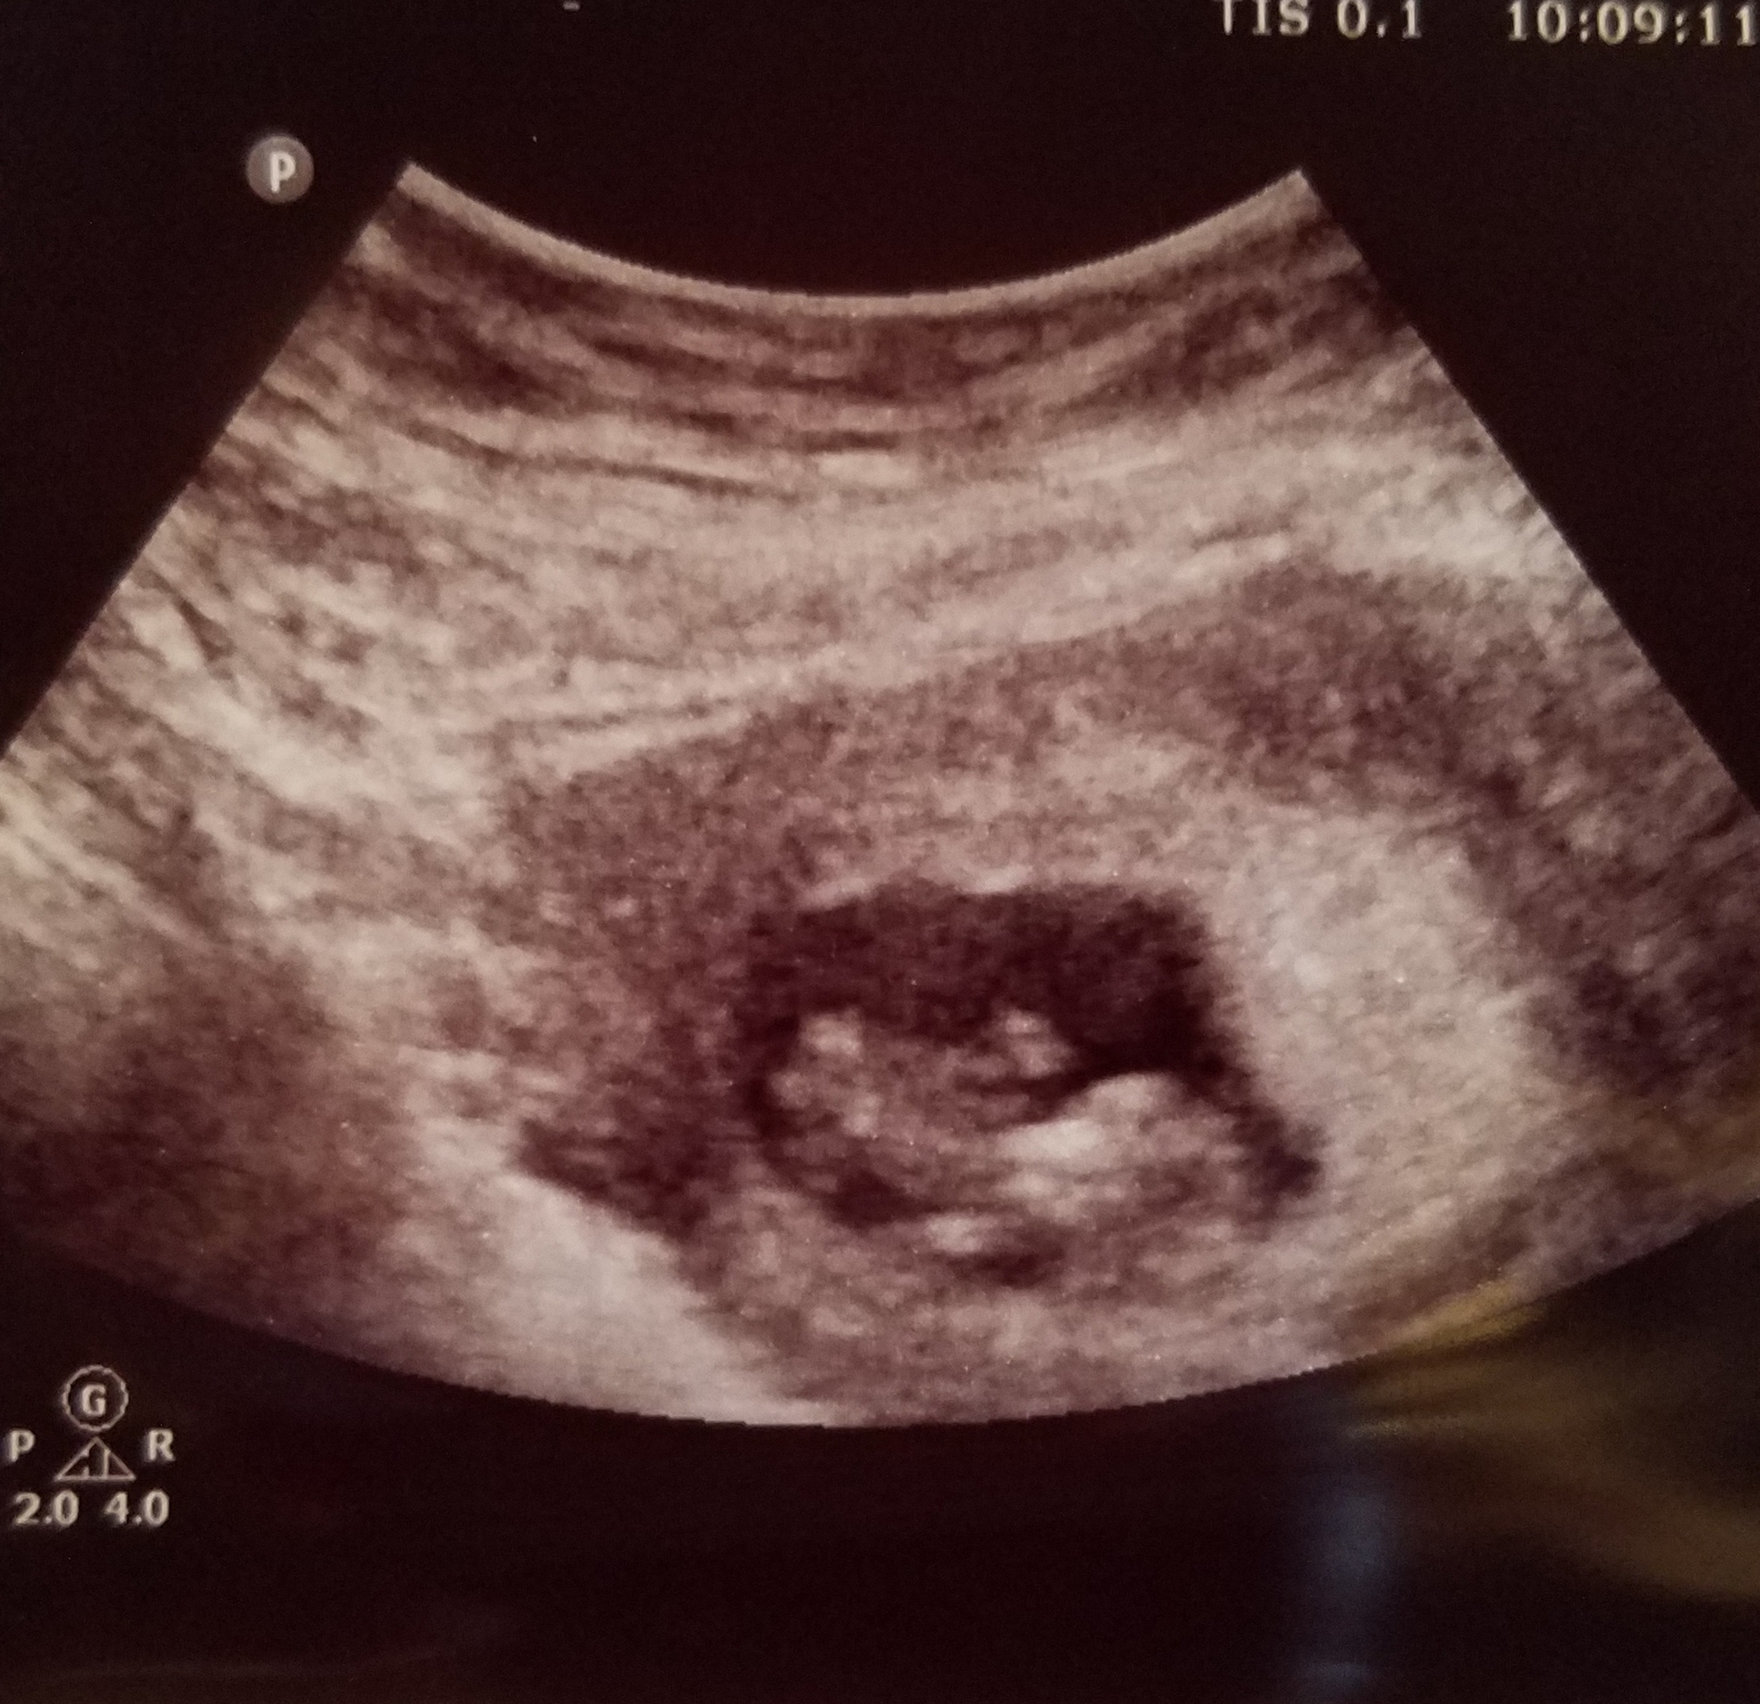

Abdominal ultrasound at 8 weeks! Baby’s heart is so strong! So in love! 🥰